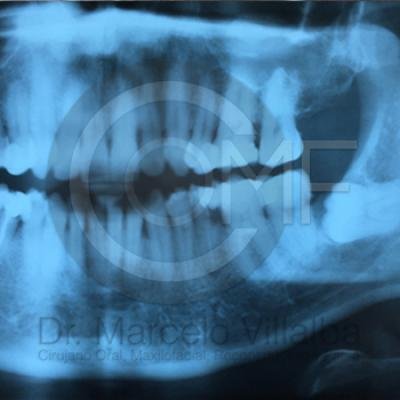

Generalmente en el momento de su erupción presentan procesos inflamatorios en la zona posterior de la cavidad oral, infección, dolor, movilidad de órganos dentarios, mal sabor en boca, mal olor en boca (halitosis), infección, incluso edema (aumento de volumen en tejido blando de la cara y/o boca) y complicaciones si no son atendidos. En el apoyo de diagnóstico se pueden requerir radiografías panorámicas y hasta tomografía en caso de ser necesarios.

Para el tratamiento de estas patologías se necesita en forma inicial estudios de laboratorio, radiografías o tomografías, estos estudios serán solicitados por el especialista a cada caso en particular, siendo su tratamiento quirúrgico bajo la modalidad de anestesia local o anestesia local más sedación consciente se puede realizar el procedimiento en corto tiempo y buen pronóstico.